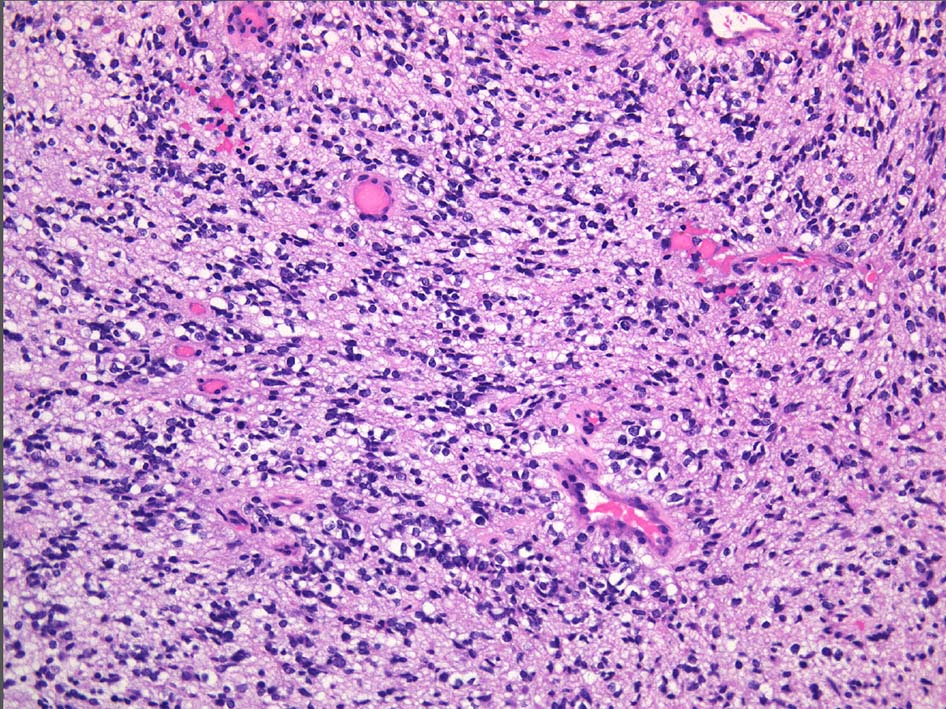

HE brain stem glioma, giant multinuclear cell+, MIB-1 50%, IDH1 R132H negative, p53++

予後はいくらもかわらない。いまのintegrated diagnosisにあわせるとやっかい。

大事なのはhistonの異常をしらべなければならない. Histon H3.1 HIST1H3BK27M

この遺伝子異常によるタンパク質は免疫染色で検出できる抗体がある。かならずしもsequenceしなくてよい.

Final integrated diagnosis

Integrated diagnosis: Diffuse midline glioma(brainstem glioma) H3K27M-mutant, WHO gradeIV

Histological diagnosis: Glioblastoma

Histological grade: Grade IV

Molecular information: